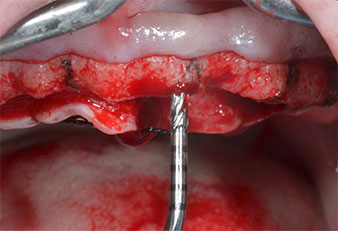

Compte tenu de la dureté relative de l’os (D2) à cet endroit, les sites recevant des implants de 10mm de long aux régions 11 et 21 ont été finalisés à l'aide d’une fraise de 4mm de diamètre, associée à un contre-angle chirurgical W&H WS-75 L, au moteur d'implantologie Implantmed de W&H ainsi qu’au module Osstell ISQ de W&H. En revanche, en raison de leur structure osseuse molle, les sites postérieurs ont été préparés en vue de l’obtention d’un diamètre final de 3mm à l'aide de l’insert Piezomed I3P. Les implants ont enfin été posés par voie transgingivale (Flap Less) pour obtenir l’ostéointégration dans un délai de trois mois (Figures 6-10). L'appareil existant a été maintenu sur quatre implants provisoires (Fig. 8).